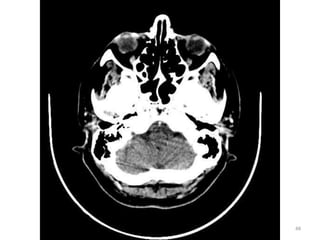

1. Cristalino do olho D.

2. Lobo parietal E.

3. Medula Oblonga

(bulbo).

4. Seio esfenoidal.

5. Corpo vítrio (globo

ocular).

6. Hemisfério cerebelar D